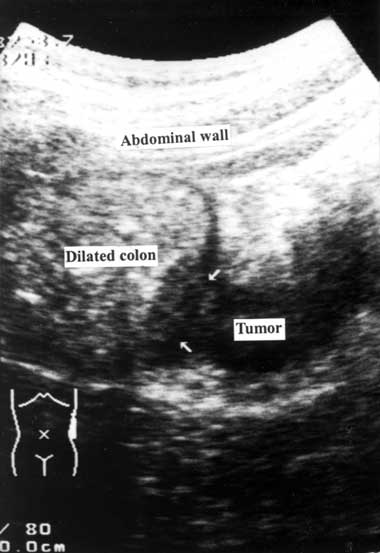

1 Longitudinal scan showing proximal colon dilatation with a mass lesion (arrows) inside the descending colon

A detailed medical history was obtained and a physical examination was performed by a member of the emergency or surgical house staff. After giving informed consent, the patient underwent an ultrasonographic examination, performed by staff emergency physicians or staff surgeons who had completed the fundamental gastrointestinal ultrasonographic training course provided by the Society of Ultrasound in Medicine, Taiwan. Ultrasonography was performed with a handheld 3.75–6 MHz curved array transducer (Toshiba SSA-340A, SSA-550A; Tochigi-Ken, Japan) over the patient’s abdomen, screening along the caecum, ascending colon, hepatic flexure, transverse colon, splenic flexure, descending colon, sigmoid colon and rectum. Any additional or abnormal ultrasonographic changes were described and the ultrasonographic diagnosis was recorded. To reduce interference from gas in the bowel (which blurs the ultrasound image), the patient’s position was changed from supine to the right or left lateral decubitus position during the ultrasonographic examination. Because normal bowel loop is compressible, an incompressible lesion within the colon or extending outside the colonic wall was suggestive of a colorectal tumour. Ultrasonographic diagnosis of a colorectal tumour was based on a proximal colon dilatation with a distal colon collapse and a mass lesion inside the transitional colon (Box 1).